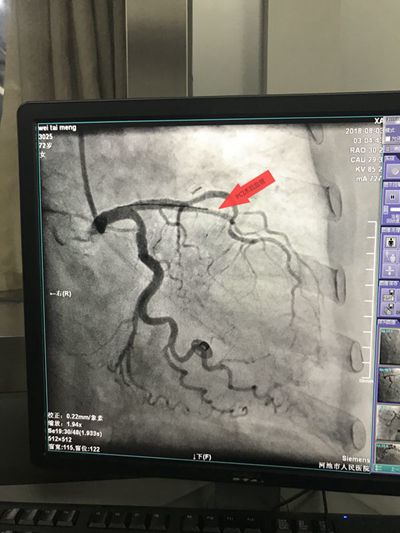

从穿刺、造影、球囊扩张......整个手术医护人员默契配合,两枚救命的支架顺利植入韦婆婆体内,整个过程用时51分钟。术后韦婆婆的胸痛症状立即得到缓解。